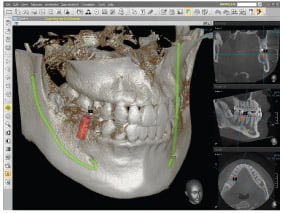

Our C.T. scanner is the E Woo Picasso scanner, used for 3D imaging of the jaws.

CT scans are 3 dimensional images of your bone – We are very proud to be only one of a few practices in Scotland to have a CT scanner in house.

Our Preferred CT Scanner is the E-Woo Picasso from Vatech & E-woo Technology, used for 3D imaging of the jaws.

Being the world’s best selling 3 in 1, Picasso trio scanners have been installed in about 2,000 sites around the world. It offers all anatomical information like septum, cyst, etc in the sinus in cases like multi or full mouth implant surgery, at once.

Below are some screen images of the information we gain that is invaluable to the dental Implant process as it allows to visualise the placement in 3D. The main benefit is that as we know the anatomy of the site where the implant is placed we do not have to make large cuts(incisions) in the gum. Implants are placed through a very small hole in the gum therefore reducing healing time and post surgery discomfort and swelling.